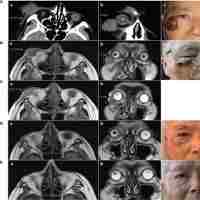

| Abstract | Perivascular epithelioid cell tumors (PEComas) are rare mesenchymal tumors. Unresectable malignant PEComas with TFE3 rearrangement have no recommended therapy to date. Here, we report the first case of malignant gastrointestinal PEComa with TFE3 rearrangement which has a response to the targeted therapy of an anti-VEGFR tyrosine kinase inhibitor (TKI), apatinib. A 31-year-old female was diagnosed with malignant gastrointestinal PEComa with TFE3 rearrangement and hepatic metastases. A resection of the giant retroperitoneal mass was performed. The patient received the anti-VEGFR TKI apatinib to treat the hepatic metastasis. The tumor remained stable during apatinib treatment and the progression-free survival (PFS) lasted about 7 months. This case suggests that targeting the VEGF/VEGFR signaling pathway may be an essential new therapeutic choice for TFE3-associated malignant PEComas. |